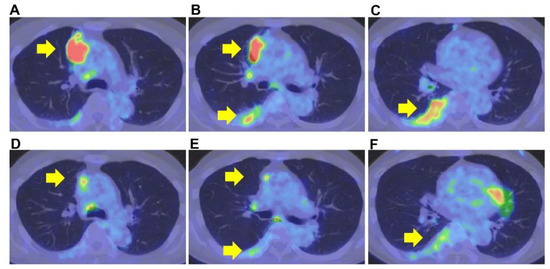

2. Case Presentation